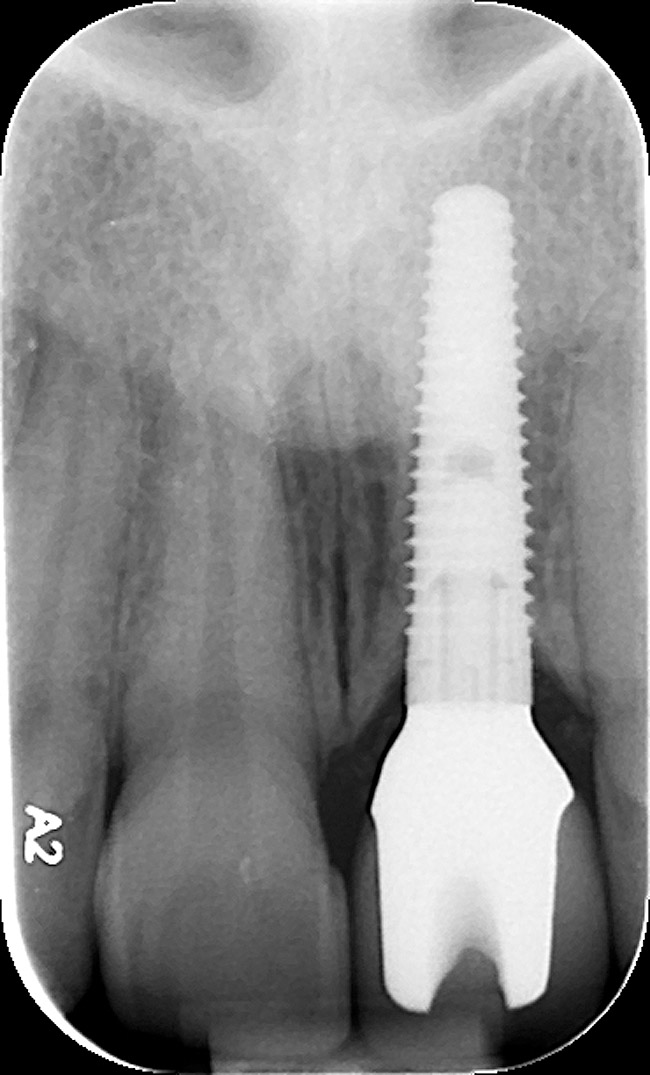

Figure 15  Regular-platform 4.3-mm x 16-mm implant positioned in osteotomy—periapical view.

Figure 15

The periodontist positioned a 4.3-mm x 16-mm regular-platform implant flush with the facial crest and 1 mm subcrestally interproximally (Figure 15), with a manually driven final seating torque value > 50 Ncm, followed by hand-tightened attachment of the immediate temporary abutment.